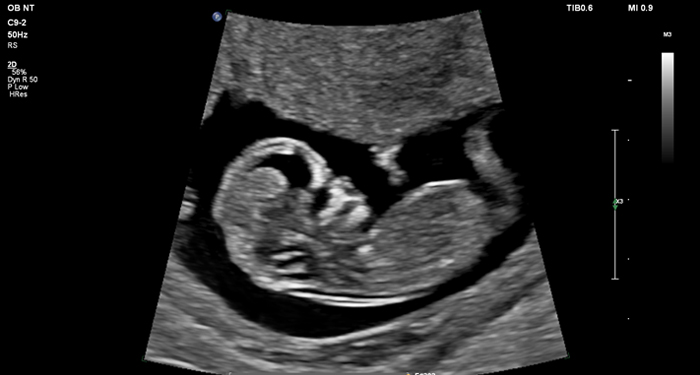

At the touch of a button, the new MaxVue high-definition display brings extraordinary visualisation of anatomy with 1,179,648 additional image pixels compared to a standard 4:3 display format mode. MaxVue enhances ultrasound viewing during interventional procedures and provides 38% more viewing area to optimise the display of dual, side/side, biplane, and scrolling imaging modes.

MaxVue offers a 38% greater viewing area.